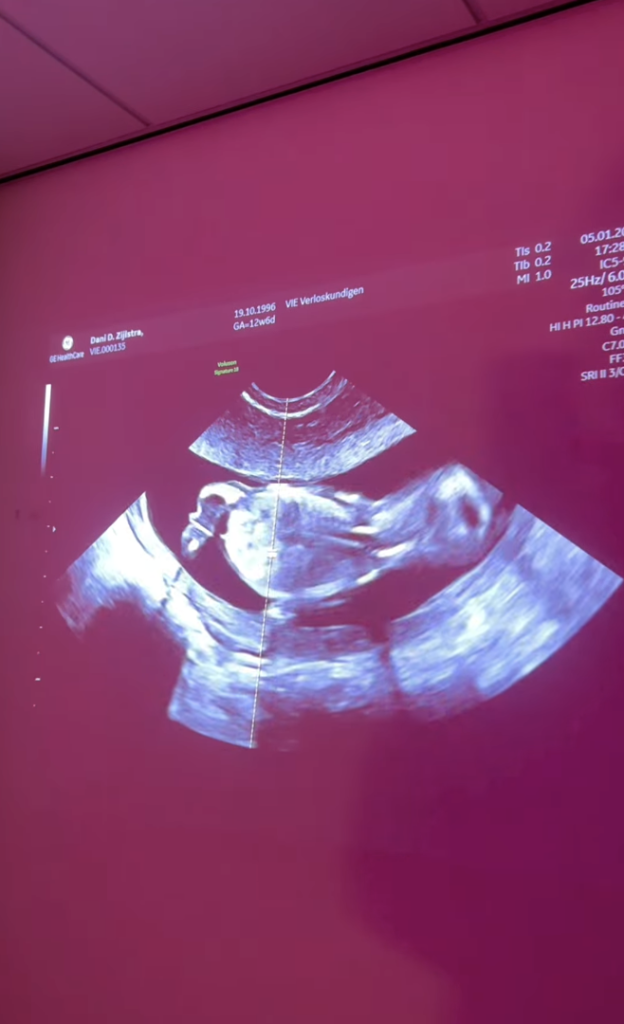

Joy van Swieten en Dani Zijlstra, die elkaar vonden in ‘B&B Vol Liefde’-2023, delen prachtig nieuws: samen verwachten ze hun eerste kindje.

De tekst gaat verder onder de foto waarop een klein wonder op beeld te zien is: de echo van Joy en Dani’s kindje.

Op Instagram laten Joy en Dani weten dat ze een klein wondertje verwachten. Ook vertellen ze dat de afgelopen maanden prachtig waren, maar dat het tegelijkertijd ‘zo intens’ was om het nieuws voor iedereen geheim te houden. Dani is ongeveer de helft van de tijd misselijk geweest, wat het soms best een uitdaging maakte. “Nu kunnen we het eindelijk met iedereen delen en daar zijn we zo blij mee.”